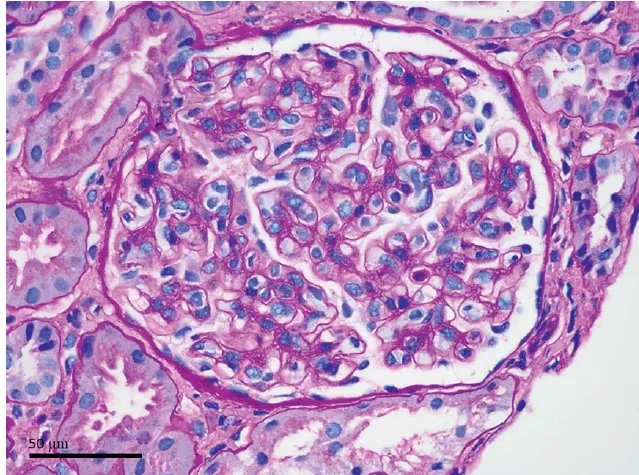

Foi realizado biópsia confirmando existência de necrose tubular aguda com cilindros biliares, compatível com Nefropatia Colêmica.

**Figura 1.** Achados urinários e histológicos da biópsia renal. (A) O sedimento urinário mostra células epiteliais tubulares, cilindros granulares corados por bile e cristais de leucina. (B) Os túbulos renais apresentam células epiteliais achatadas e perda da borda em escova (NTA). (C) Os túbulos exibem cilindros amarelo-esverdeados corados por bile (H&E).

A biópsia mostrou:

• necrose tubular aguda difusa,

• cilindros biliares verde-amarelados ocupando túbulos,

…selando o diagnóstico de Nefropatia Colêmica.